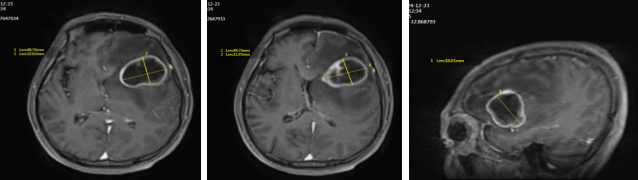

● 2024年12月23日头颅MRI平扫+增强:左侧额叶占位,考虑转移,不排除脑胶质瘤(最大直径71mm)。

头颅MRI增强(2024年12月23日)

● 2025年1月16日头颅MRI增强:左侧额叶占位,考虑转移,较前明显增大,中线移位。

头颅增强MRI